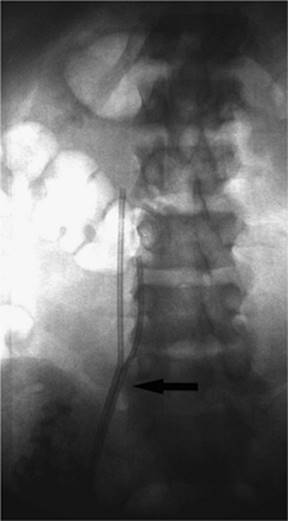

000452

Figure 35.22. Attempted canalization of the portal vein during a transjugular intrahepatic, portacaval shunting (TIPS) procedure. This CO2 injection identifies canalization of the hepatic artery (black arrow).

Puncturing the portal vein has proved to be difficult in some cases. Thrusting a large needle blindly through the liver parenchyma can cause a host of complications including bleeding from the liver capsule if the needle perforates the capsule of the liver. Hemobilia can be seen if the needle perforates a bile duct in close proximity to a vascular structure. The needle may leave the capsule of the liver and puncture adjacent organs including the intestine, gallbladder, kidney, and aorta, among others (Figs. 35.22–35.24).